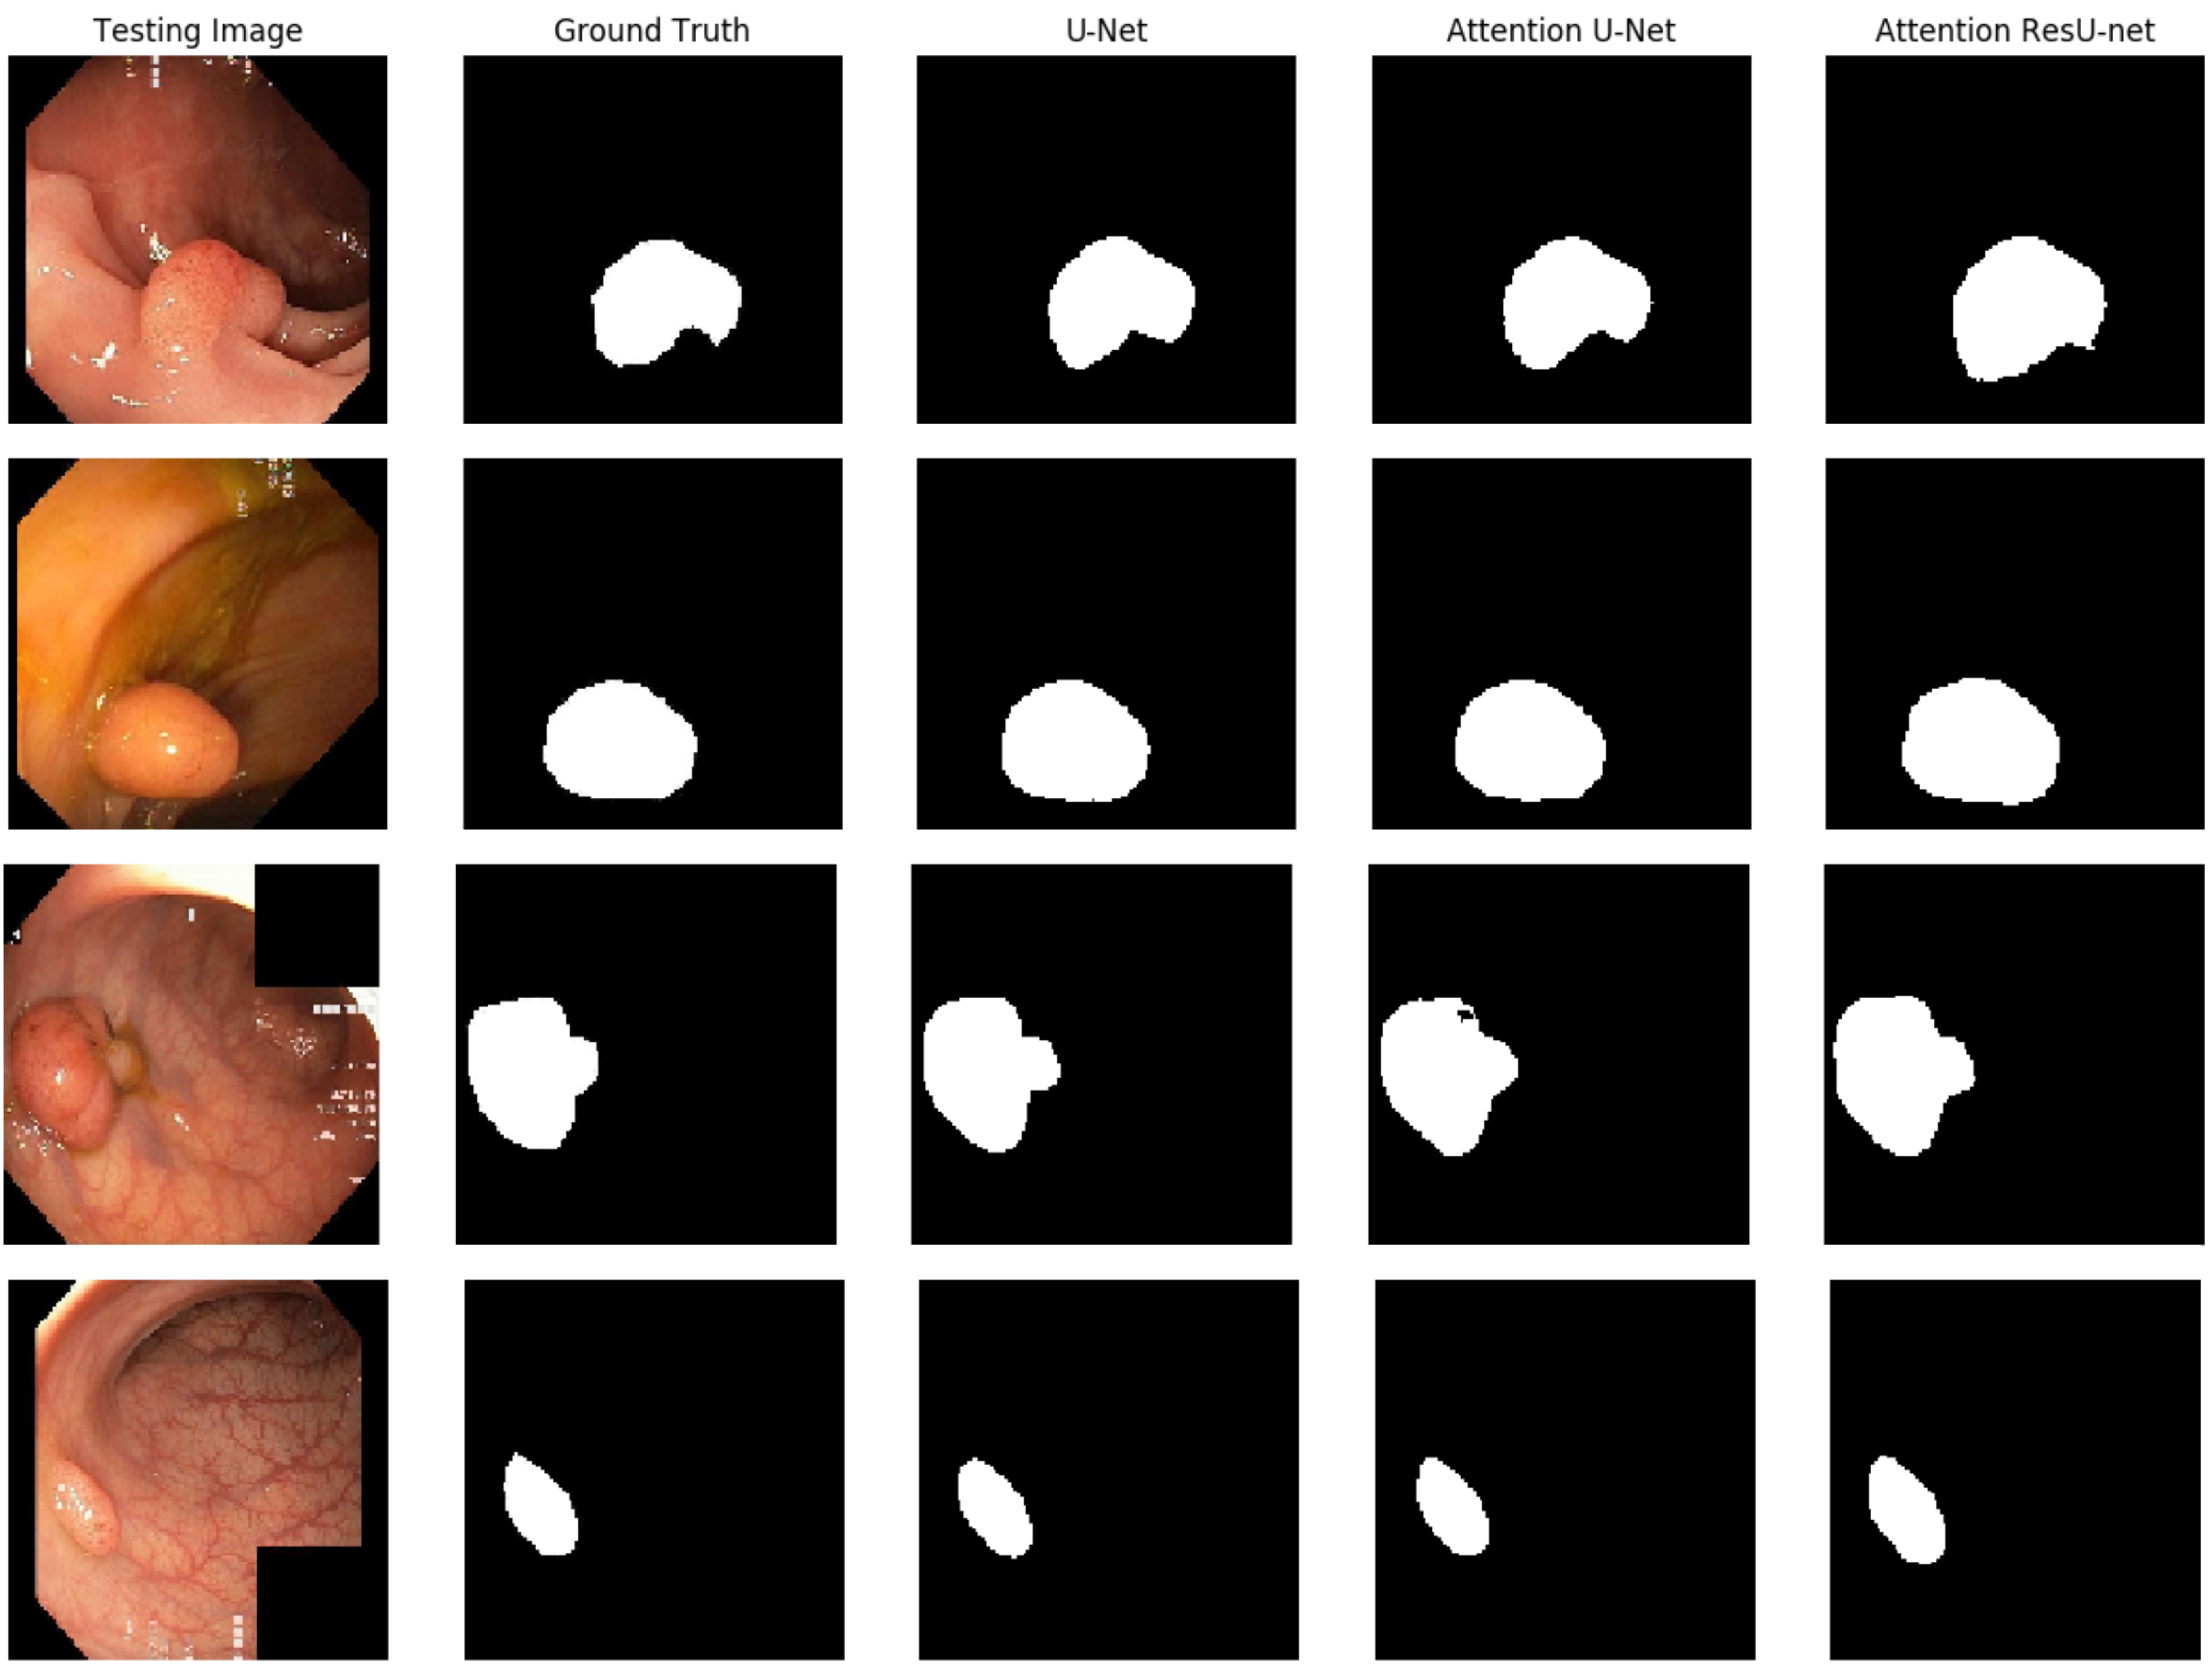

In Figure 7, we demonstrate some qualitative endoscopic lesion segmentation findings from the MICCAI 2017 test set acquired by using several approaches. The four original images show varied lesions in regard to appearance and size, and there are no apparent structural borders between normal and lesion areas. Furthermore, certain areas with poor quality make data analysis difficult. All of these present challenges in distinguishing aberrant from normal areas. However, we can observe that the segmentation of our suggested AttResU-Net is close to the ground truth. On the contrary, other methods can capture big abnormal regions successfully but may miss certain tiny abnormal regions.

Figure 7. Qualitative results comparison on the MICCAI 2017 dataset.